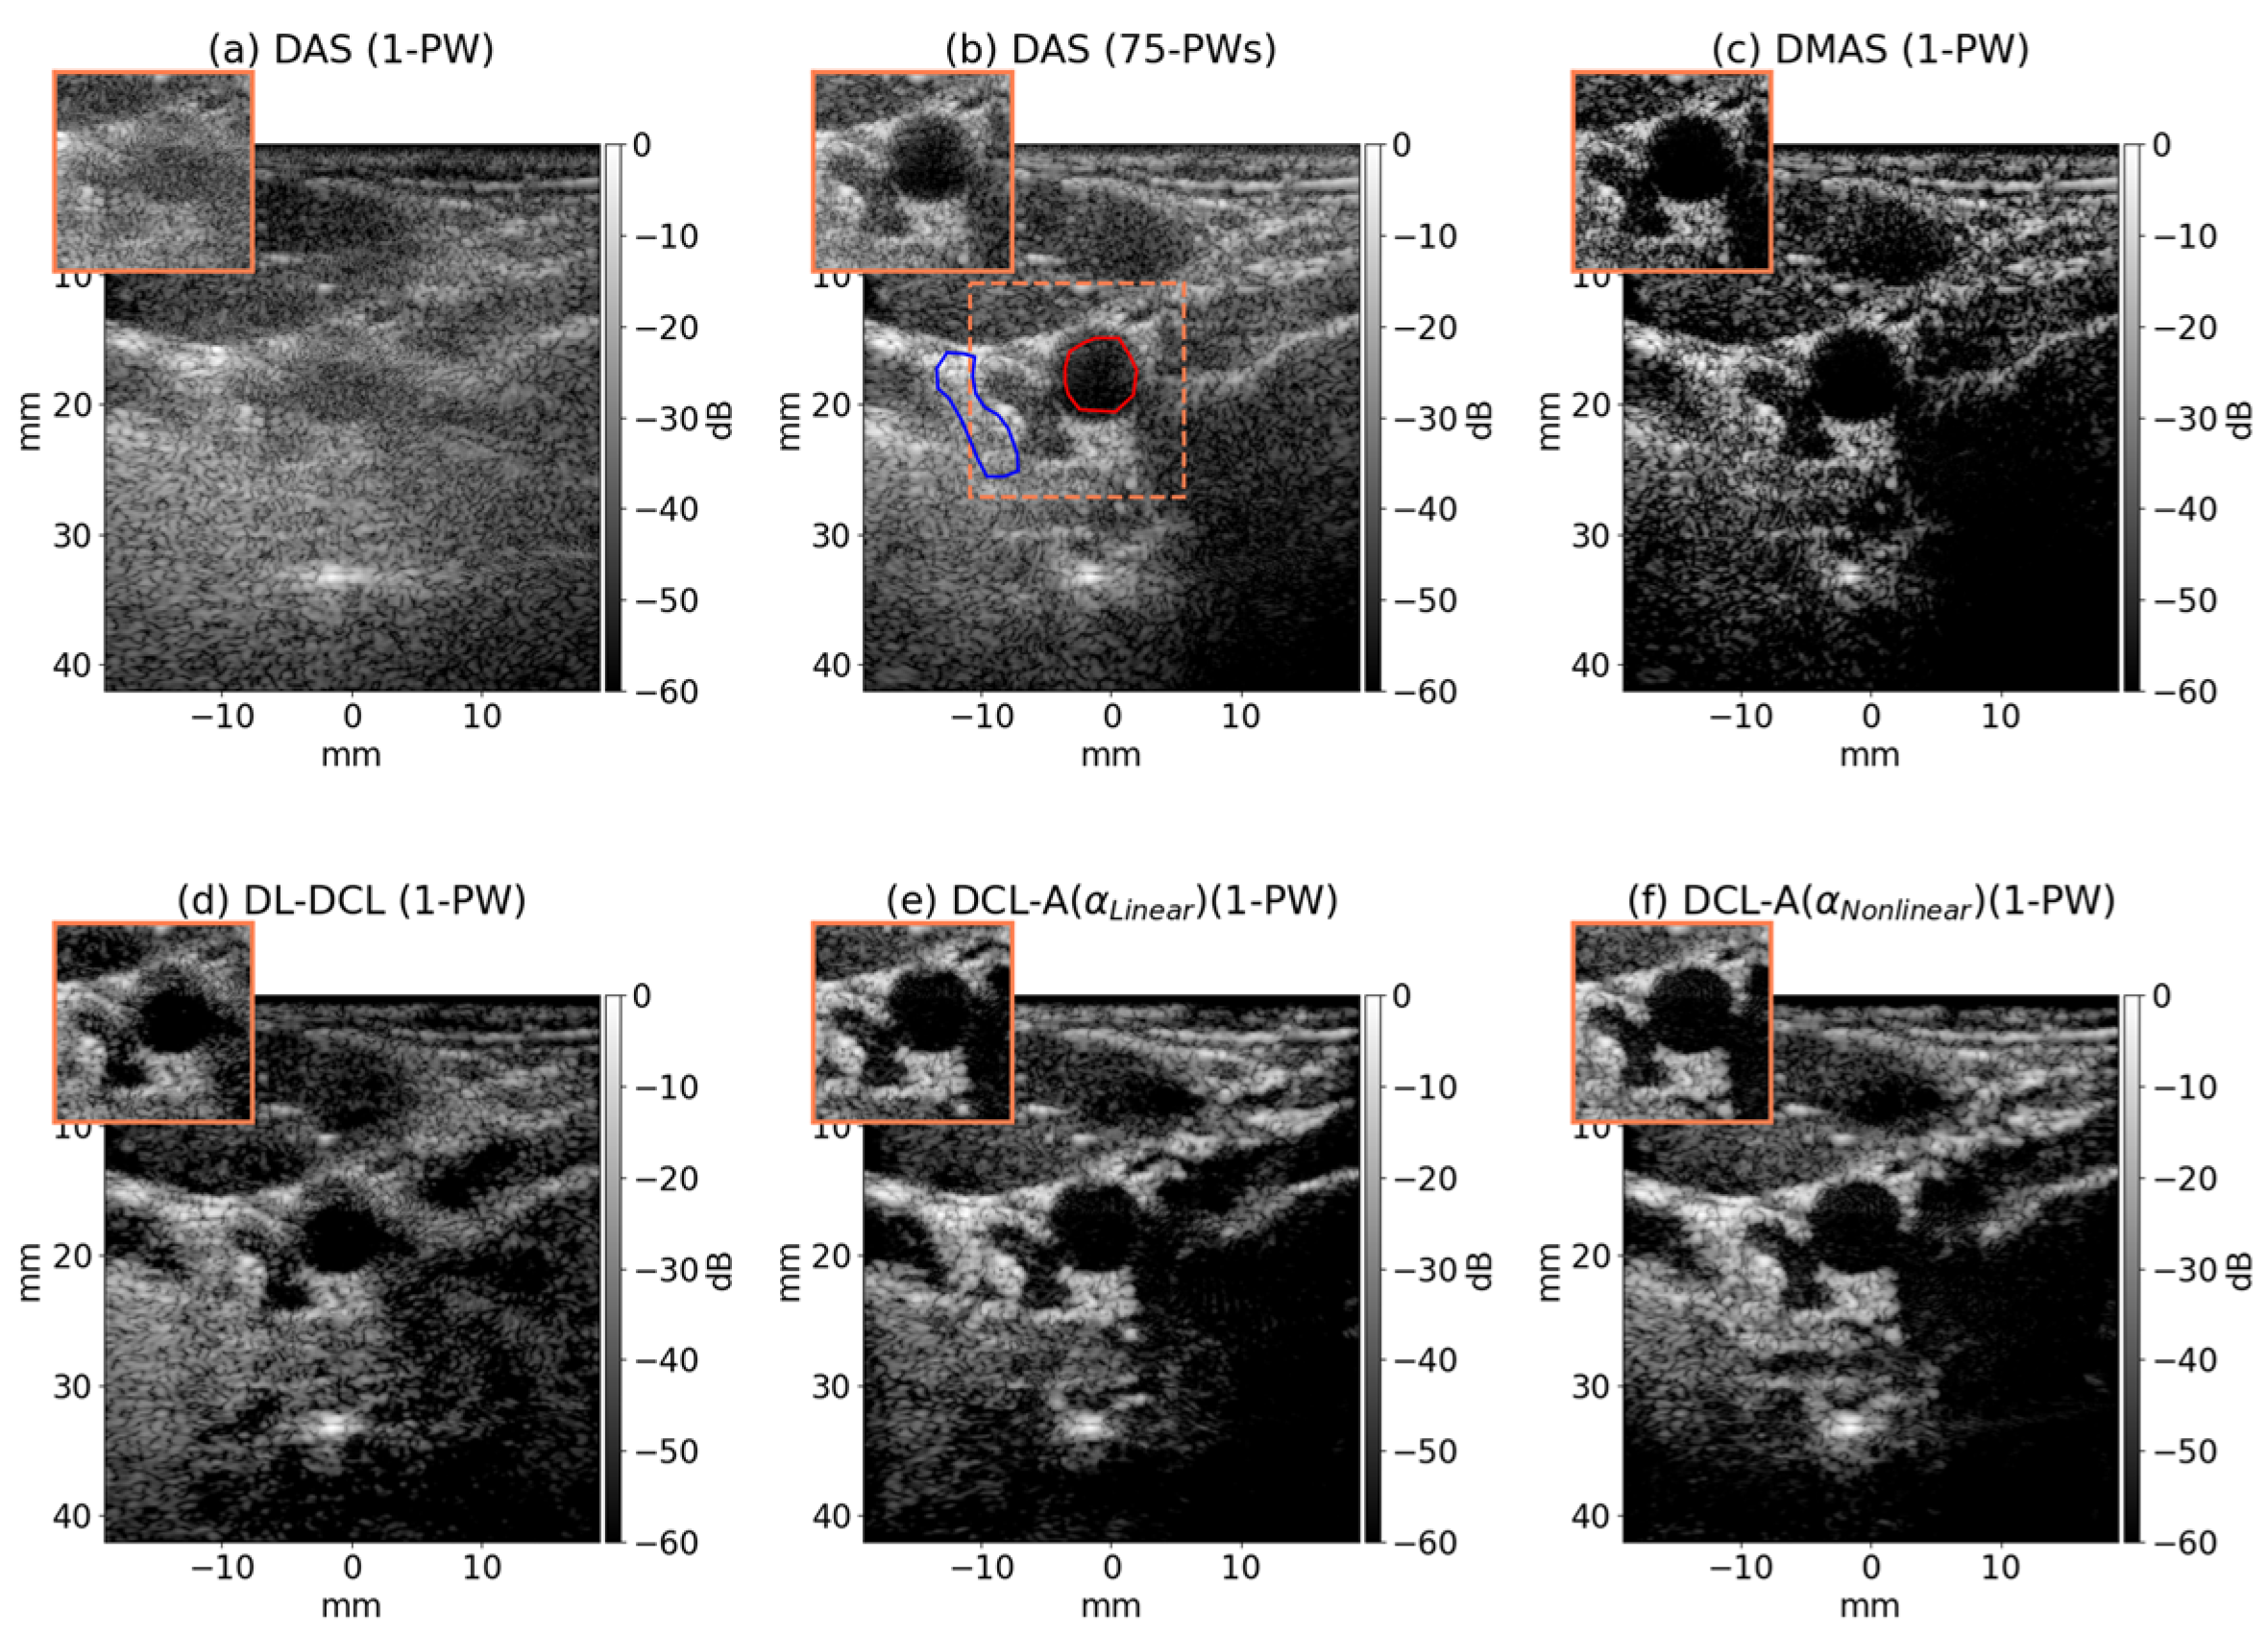

| DAS (1-PW) | DAS (75-PWs) | DMAS | DCL | DCL-A ) | DCL-A ) | |

|---|---|---|---|---|---|---|

| CNR [dB] | 1.61 | 4.43 | 3.15 | 5.68 | 5.65 | 5.70 |

| gCNR | 0.62 | 0.96 | 0.89 | 0.95 | 0.94 | 0.97 |